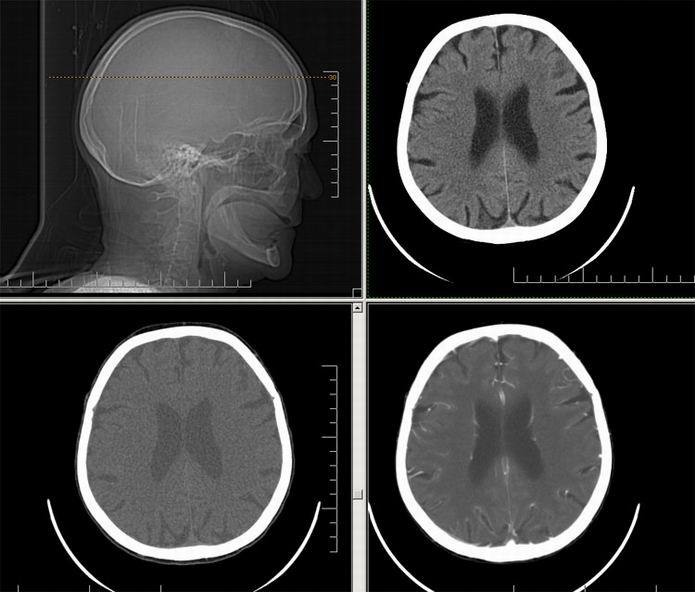

Est ce que qqun a des coupes axiales de crâne pour m'aider à réviser mon anatomie. Merci

Pour compléter tes révisions, Poupette vient de nous faire parvenir ces planches bien utiles: Planches de coupes axiales cérébrales, dans la rubrique COURS / ANATOMIE